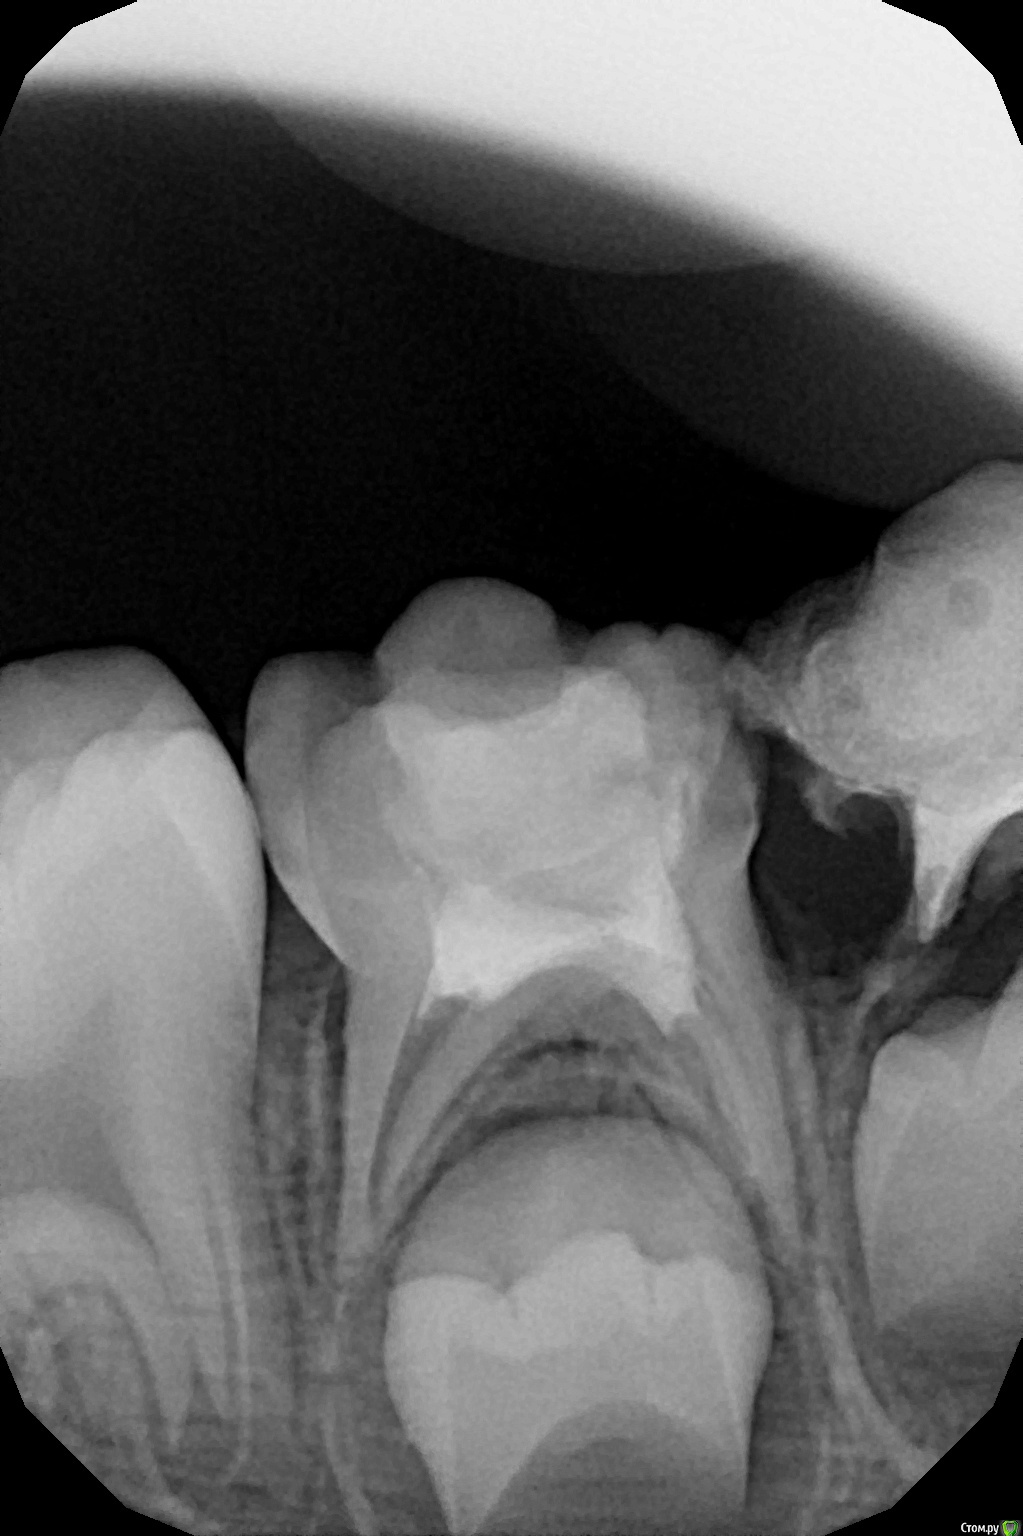

crown Опубликовано 25 июня, 2016 Поделиться Опубликовано 25 июня, 2016 Сегодня лечил 55. У меня возникло 2 вопроса. 1. На медиальном корне апикальный периодонтит, или это все пришло с бифуркации и малой кривизны? 2. МБ2 нужно искать, он вообще бывает в молочных? Ссылка на комментарий

Джима Опубликовано 25 июня, 2016 Поделиться Опубликовано 25 июня, 2016 1. crown, а какая, по большому счёту, разница?2. есть очень часто. если могу расковырять - расковыриваю, если не могу - значит, не судьба. у них кроме мб2 ещё много чего есть. Ссылка на комментарий

crown Опубликовано 25 июня, 2016 Поделиться Опубликовано 25 июня, 2016 1. crown, а какая, по большому счёту, разница?2. есть очень часто. если могу расковырять - расковыриваю, если не могу - значит, не судьба. у них кроме мб2 ещё много чего есть.Ну как, если инфекция в апикальной трети то нужно полностью проходить канал, а не на 2\3 как мы обычно делаем. Просто пропущенный мб2 в шестерке периодонтитной дает о себе знать со временем, т. к. там все таки есть инфекция. Ссылка на комментарий